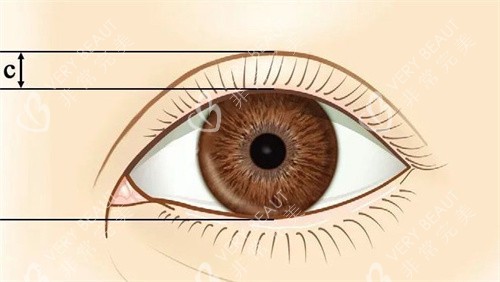

胡立强医生是慈溪人民医院整形外科的“老牌子”,卫健委备案显示他从业12年,主攻眼部精细化整形。他的“杀手锏”是显微镜下小创口缝合——切口只有2-3毫米,术后7天拆线时,小林对着镜子惊呼:“这疤淡得像蚊子咬的!”更绝的是,他擅长根据脸型设计“妈生款”眼型:圆脸配开扇形,长脸配平扇形,连眼尾上扬角度都要拿卡尺量。

陈晓峰是慈溪人民医院整形外科的“鼻整形担当”,卫健委官网显示他每年完成鼻部手术超200例,擅长用自体软骨+膨体复合材料打造“伪素颜鼻”。他的“微调哲学”很接地气:“鼻子是五官的‘中轴线’,0.5毫米的偏差,结果可能差十万八千里。”